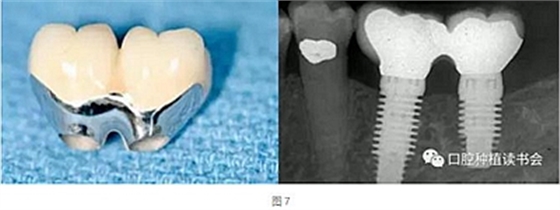

天然牙的預(yù)備通常限制刃狀邊緣的使用以避免最終修復(fù)體外形過(guò)凸。沒(méi)有具體的研究表明凹形邊緣完成線比其他的完成線形態(tài)更優(yōu)越,但易于預(yù)備的特點(diǎn)是選擇它們的理由,而且避免了修復(fù)體過(guò)大。修復(fù)學(xué)中存在幾種常見的刃狀邊緣預(yù)備的適應(yīng)證,因?yàn)樗鼈冎恍枰獦O小的切削量。適應(yīng)證包括:①種植體基臺(tái)(圖7);②磨牙和前磨牙的根分叉區(qū)域;③下頜切牙的鄰間隙區(qū)域;④下頜后牙的舌側(cè)面;⑤軸面特別凹(非常凸的軸向表面);⑥傾斜超過(guò)15°的基牙軸面。

種植體基臺(tái)使用刃狀邊緣的一個(gè)例外是當(dāng)種植體過(guò)于偏頰側(cè)或距離鄰牙過(guò)近,同時(shí)要制作瓷冠邊緣時(shí)。在種植體位置過(guò)于偏頰側(cè)的情況下,可以選擇肩臺(tái)或淺凹邊緣的冠邊緣設(shè)計(jì),為修復(fù)創(chuàng)造足夠的空間并避免修復(fù)體外形過(guò)凸(圖8)。粘接固位基臺(tái)邊緣的位置要位于游離齦緣1±0.5 mm的范圍內(nèi),過(guò)深的邊緣容易導(dǎo)致粘接劑殘留,造成種植體周圍炎(圖9)。